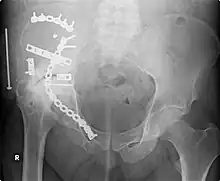

External fixation of fractures was refined by American surgeons during the Vietnam War, but a major contribution was made by Gavril Abramovich Ilizarov in the USSR. He was sent, without much orthopedic training, to look after injured Russian soldiers in Siberia in the 1950s. With no equipment, he was confronted with crippling conditions of unhealed, infected, and misaligned fractures. With the help of the local bicycle shop, he devised ring external fixators tensioned like the spokes of a bicycle. With this equipment, he achieved healing, realignment, and lengthening to a degree unheard of elsewhere. His Ilizarov apparatus is still used today as one of the distraction osteogenesis methods.[12]

- Orthopedic trauma